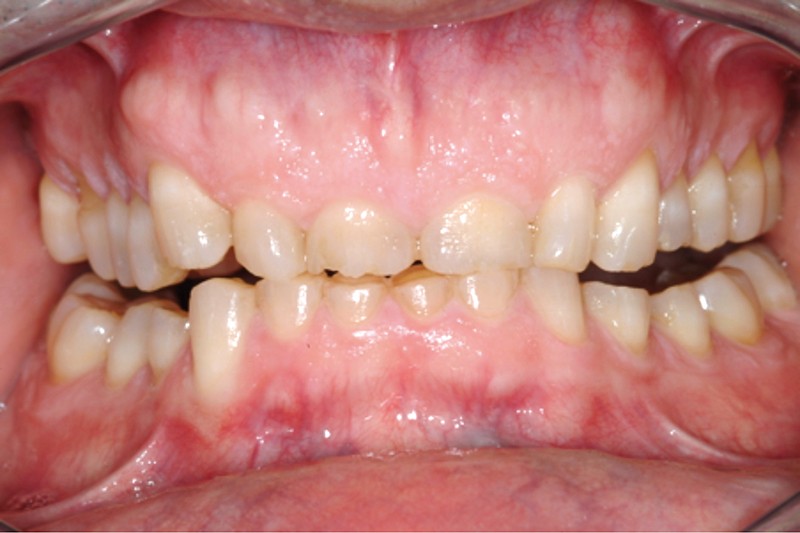

Jean-Pierre Attal : Exactement, car il est possible d’appliquer le protocole de la technique « 3 steps » aux patients présentant des pertes de substance d’origine attritive (bruxisme) (fig. 5).

Pour autant, Francesca Vailati exposera les précautions particulières à prendre dans ce contexte dysfonctionnel. Le principe du traitement est de protéger rapidement la dentine par collage (uniquement des restaurations par addition afin de ne pas délabrer davantage les dents déjà altérées) et de permettre ainsi au patient de dégrader les restaurations plutôt que l’organe dentaire.